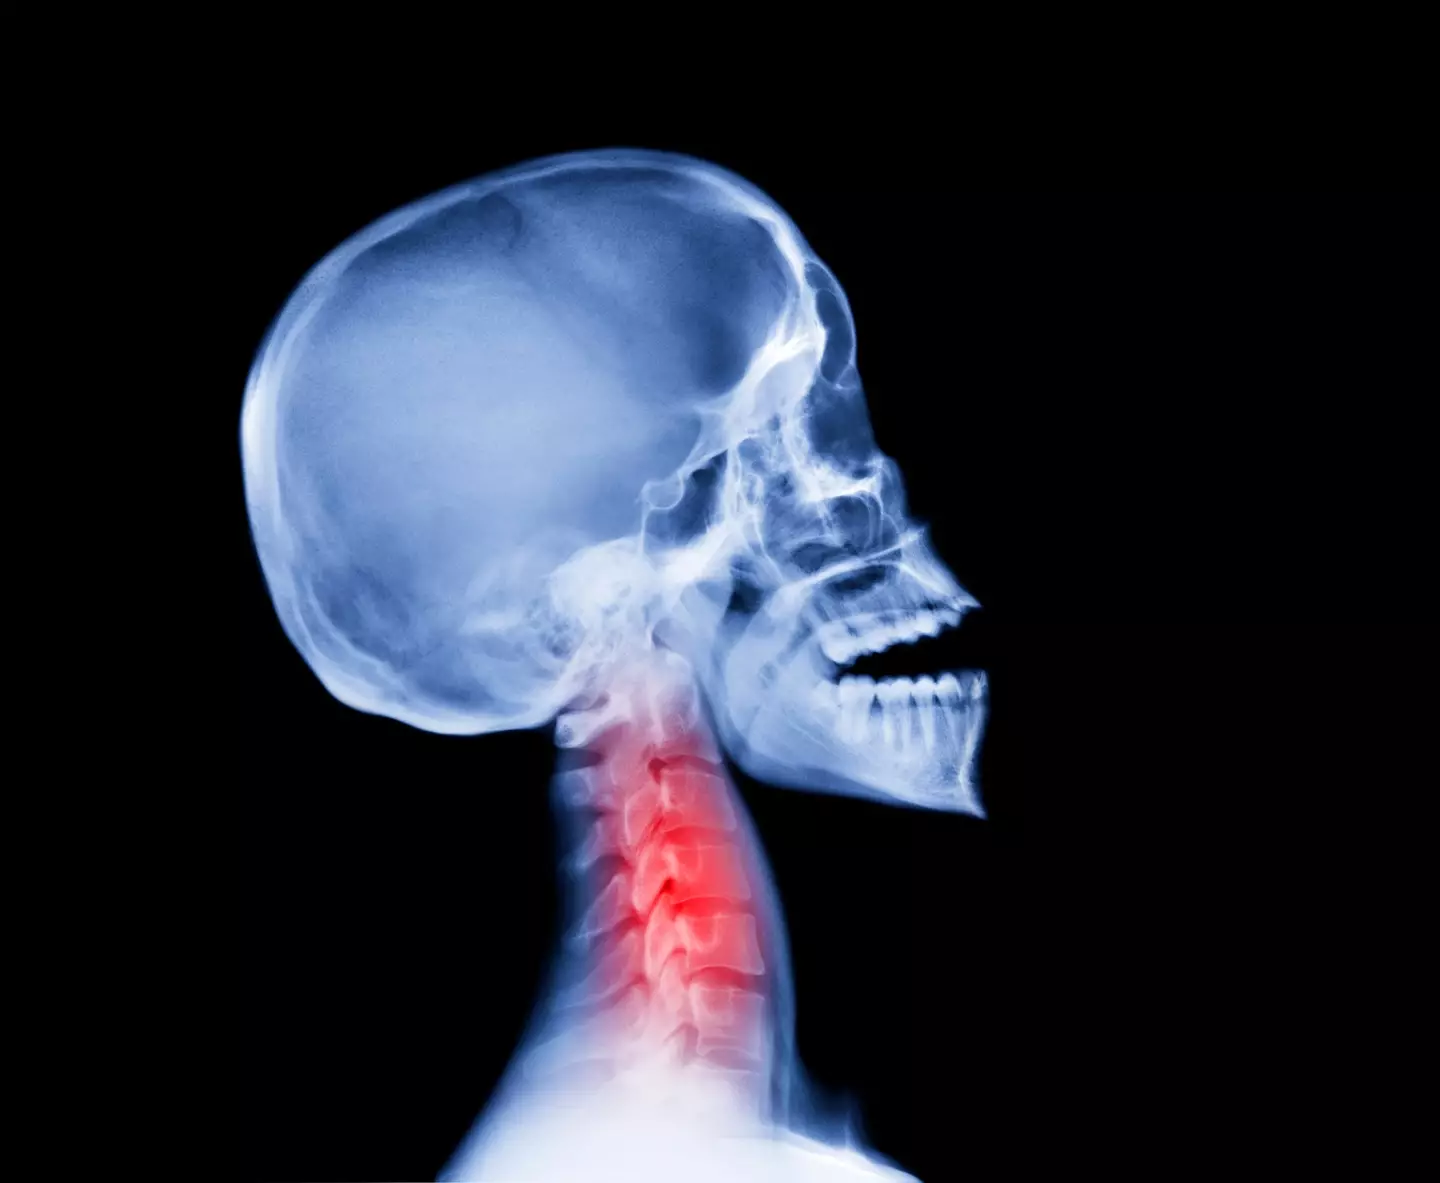

Oropharyngeal cancer is a type of head and neck cancer.

It is found in the central section of the throat, behind the mouth.

This area covers parts such as the soft palate and tonsils, but also includes the back of the tongue and the sides and back of the throat.